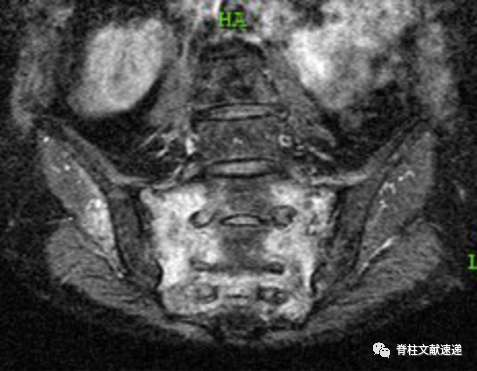

局部疼痛常见,压痛叩击痛常阳性,部分患者存在体位变化时疼痛,与骨质疏松性胸腰椎骨折相似。骶骨衰竭骨折常见于骶骨翼。X线和CT不易诊断,MRI和骨扫描是推荐的影像学检查,敏感度接近100%。成像特点和骨质疏松性胸腰椎压缩骨折类似,MRI T1低信号,T2和脂肪抑制像呈片状高信号。如下图所示,骶骨MRI显示双侧骶骨翼冠状图像上信号增加,表明双侧骶骨翼骨折引起明显的骶骨水肿。